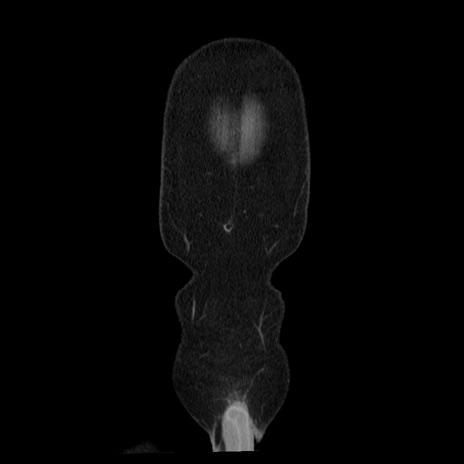

症例29(冠状断像)

【症例】40歳代男性

【現病歴】2日前から胃痛あり。徐々に周期的な激痛に変化した。本日になっても激痛があるため受診。

【身体所見】意識清明、BT 38-39℃台あり、腹部:膨満、やや硬、右下腹部に圧痛あり。

【データ】WBC 8500、CRP 23.26